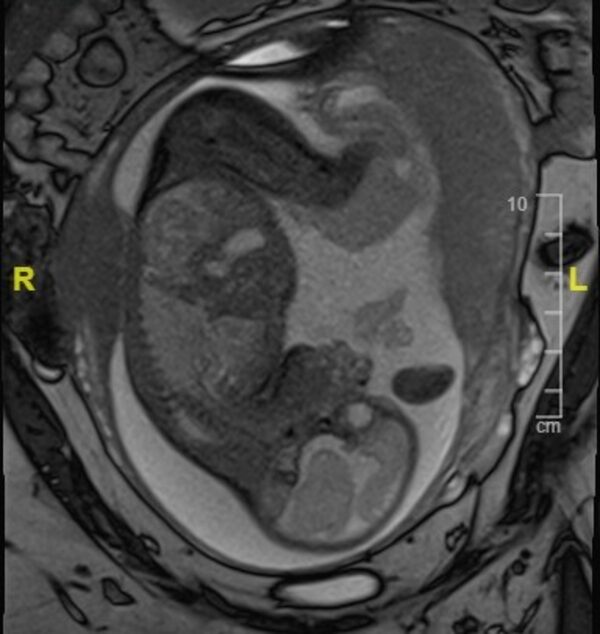

Five weeks after Ms. Morris's surgery, an MRI of the fetus – then 29 weeks and two days old – gave the medical team a clearer idea of how the brain was developing.